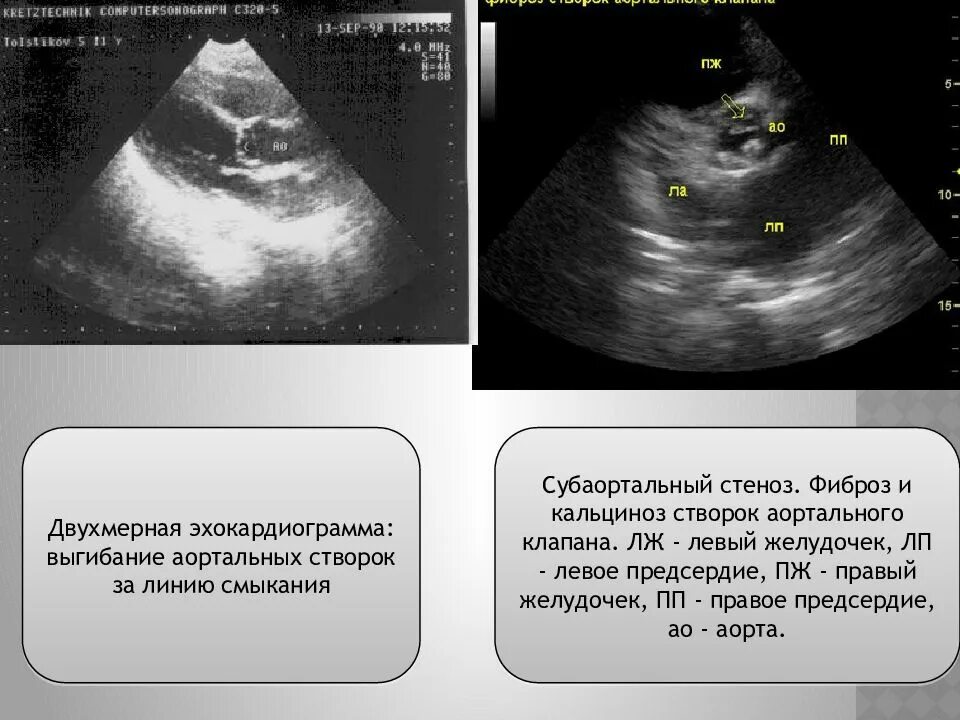

Уплотнение аортальных створок